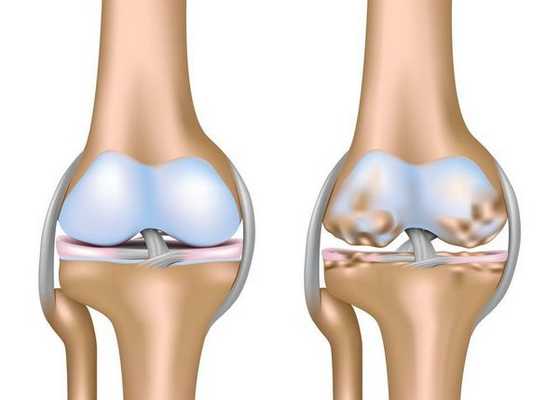

Артроз коленного сустава (гонартроз) — это прогрессирующее хроническое заболевание коленных суставов с повреждением, истончением и разрушением его хрящевой части (суставные поверхности бедренной и большеберцовой костей), а также поражением субхондральной кости. [2] [5] [16] Доказано исследованиями (артроскопия и МРТ), что помимо поражения суставного хряща в процесс вовлекаются мениски и синовиальная оболочка. Гонартроз — одна из самых распространенных ортопедических патологий. [4] [6] [9] [22] Существуют его синонимы — остеоартроз (ОА), деформирующий артроз. Заболевание является важной социально-экономической проблемой, так как широко распространено и значительно ухудшает качество жизни больных из-за постоянного болевого синдрома и, кроме того, становится причиной высокой инвалидизации. [15] [27]

До середины восьмидесятых годов прошлого века не было унифицированного определения заболевания. Только к 1995 году комитетом по остеоартрозу Американского колледжа ревматологии заболевание было охарактеризовано как результат действия механического и биологического факторов, приводящих к дисбалансу между процессами деградации и синтеза внеклеточного матрикса суставного хряща. [11] [19] В итоге происходит его разволокнение и дегенерация, образуются трещины, остеосклероз и уплотнение кортикального слоя субхондральной кости, растут остеофиты и формируются субхондральные кисты. [12] [29]

Первая стадия заболевания характеризуется первичными изменениями в гиалиновом хряще. [12] [18] Костные структуры не затрагиваются. Во внутрикостных сосудах и капиллярах нарушается кровоснабжение. Становится сухой поверхность хряща, и он утрачивает свою гладкость. Если заболевание сопровождается постоянным напряженным синовитом, то развивается киста Бейкера (грыжевое выпячивание капсулы сустава подколенной области). [15] После значительной нагрузки на сустав возникают тупые боли. Возможна небольшая отечность, которая проходит после отдыха. Деформации нет.

Гонартроз, II стадия

На второй стадии хрящевая прослойка резко истончается, а местами и вовсе отсутствует. [22] Появляются остеофиты по краям суставных поверхностей. Изменяются качественные и количественные характеристики синовиальной жидкости сустава — она становится гуще, более вязкой, что приводит к ухудшению питающих и смазывающих свойств. [14] [16] Боли более продолжительные и интенсивные, часто при движении появляется хруст. Отмечается незначительное или умеренное ограничение движений и небольшая деформация сустава. Прием анальгетиков помогает снять болевой синдром.

Гонартроз, III стадия

Отсутствие хряща на большинстве поражённых участков, выраженный склероз (уплотнение) кости, множество остеофитов и резкое сужение или отсутствие суставной щели. [8] [15] Боли практически постоянные, походка нарушена. Подвижность резко ограничена, заметна деформация сустава. Препараты НПВС, физиопроцедуры и другие стандартные методы лечения артроза коленного сустава неэффективны. [11]